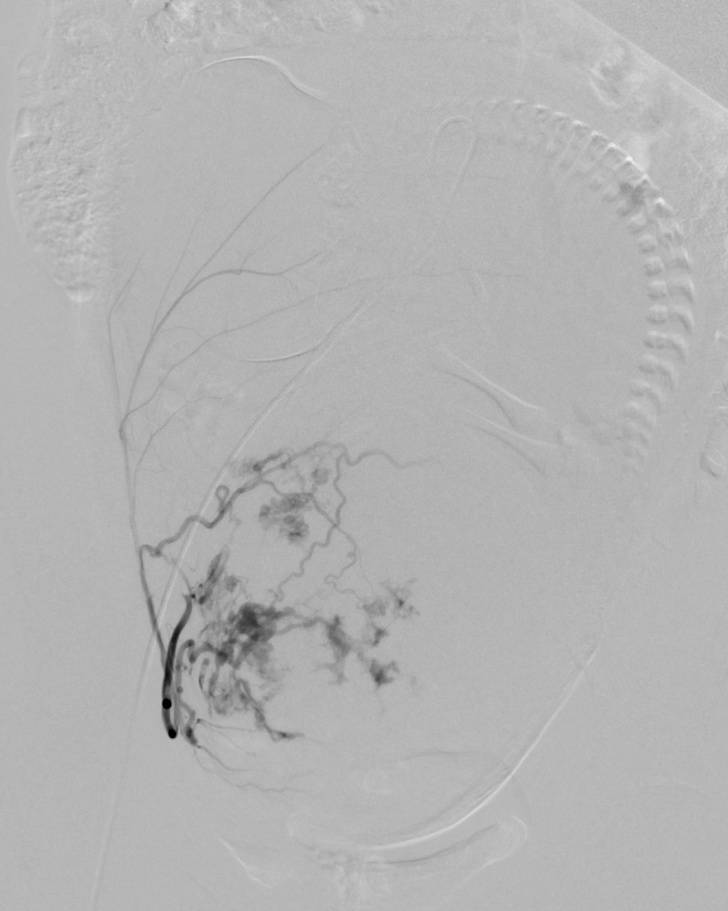

在DSA下能清楚的看到子宫中胎儿的形状(脊柱、颅脑、四肢),还不停的在胎动。介入治疗用明胶海绵栓塞双侧子宫动脉减少子宫的供血图一(左侧子宫动脉栓塞前后,右侧同左侧)。

图一:左侧子宫动脉栓塞前

图一:左侧子宫动脉栓塞后

当双侧的子宫动脉栓塞结束后,小BABY已经没有了胎动,说到这读者应该明白是怎么回事了,凶险型前置胎盘伴胎盘植入者剖宫产术中平均出血量高达3000~5000 ml,甚至高达10000 ml以上,严重威胁孕产妇生命安全。既往凶险性前置胎盘剖宫产术后为止血而切除子宫,术中平均失血量仍达为3000-5000ml。为减少出血保留子宫,产科以往采取结扎髂内动脉或子宫动脉,然而对于凶险性前置胎盘并伴有胎盘植入的患者,即使结扎髂内或子宫动脉,也无法完全阻断胎盘植入部位的血供,并且剖宫产术中因出血量大,行髂内或子宫动脉结扎难度增大。近年来球囊导管技术已越来越多的应用于凶险型前置胎盘伴胎盘植入剖宫产术。由于孩子太大避免手术出血过多介入科医生在腹主动脉双侧肾动脉下方放置了球囊导管阻断腹主动脉下端的血供图二。